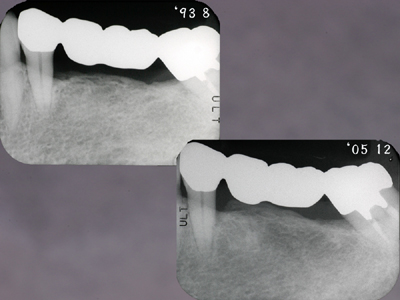

浮腫性の歯肉、全顎にわたりpd8〜10mm、著しい動揺がみられる重症例です。

1ヶ月後、プロービングデプスは2〜3mmに改善しました。

メインテナンス3年が経過しました。再発もみられず安定しています。